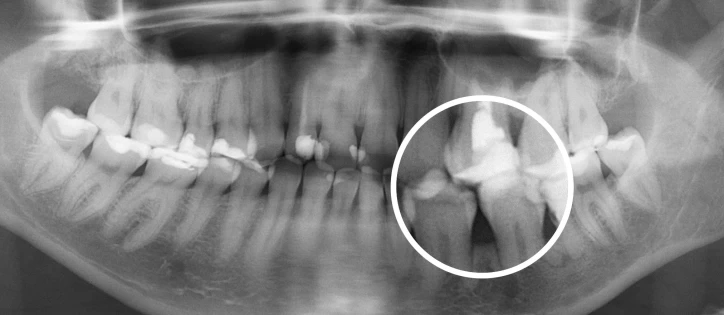

- Диагностика. Направляем на диагностические процедуры – фотопротокол, снятие цифровых оттисков, рентген и КТ. Собираем максимум информации о состоянии полости рта.

- Моделирование лечения. Используем искусственный интеллект для просчета хода коррекции зубного ряда. Проверяем вариант с удалением восьмерок и без. Объясняем, если без удаления зубов мудрости не обойтись. На этом этапе показываем вам, как будет пошагово происходить ортодонитческая коррекция и какой результат вы получите.